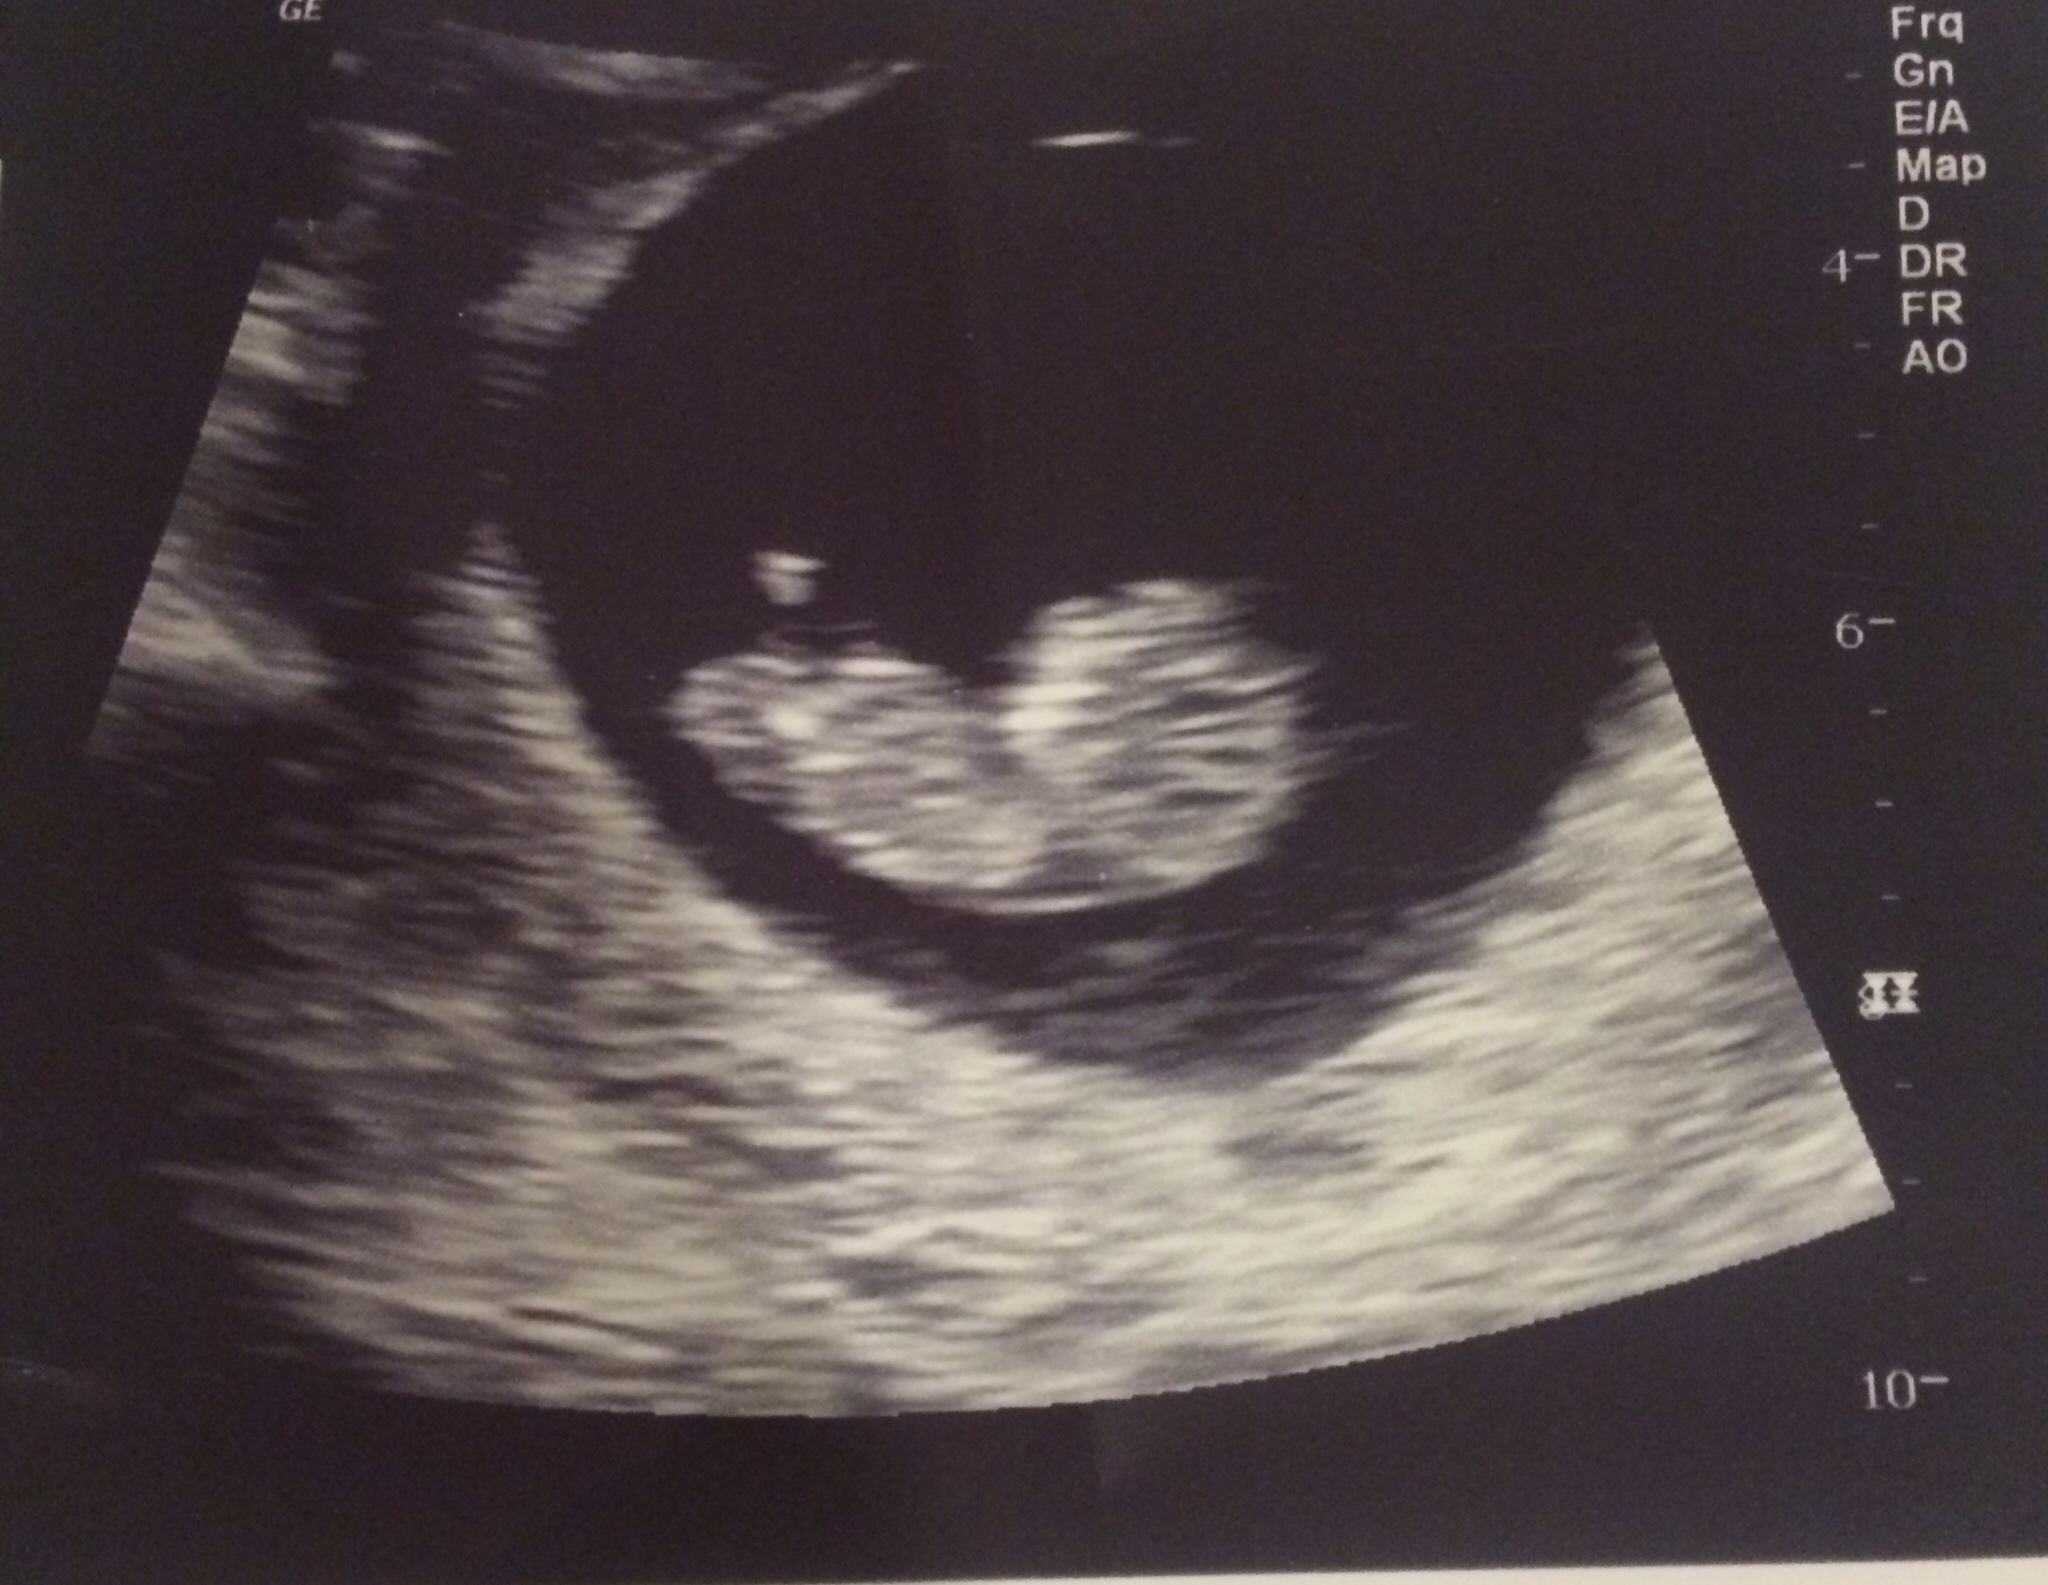

Here is my squirmy baby at 11 w 1d

This little one will be my first baby and it is due on September 17th, which is my birthday!!! LMP and dating u/s at 7 weeks matched perfectly for 9/17 EDD. I can't believe it!!